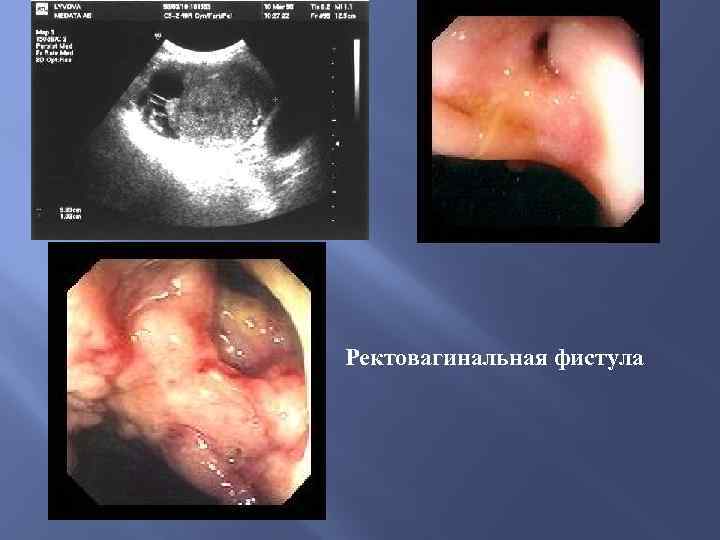

Ректовагинальная фистула

Ректовагинальная фистула